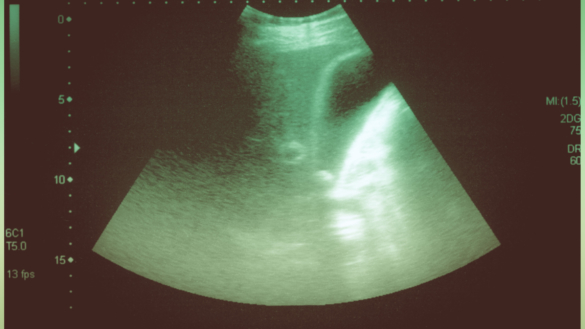

När din gallblåsa undersöks efter inflammation går man vanligtvis igenom symtomen samt en utvändig undersökning där man kontrollerar om magen är öm kring platsen. Det är vanligt att blodtryck, andning och saturation mäts för att se hur allvarliga problemen är.

En undersökning med ultralljud brukar göras för att bekräfta diagnosen. Några andra undersökningar som ibland görs är datortomografi, magnetresonansundersökning och ECRP. Under en ECRP-undersökning kan man i vissa fall också ta bort gallstenar under undersökningens gång.